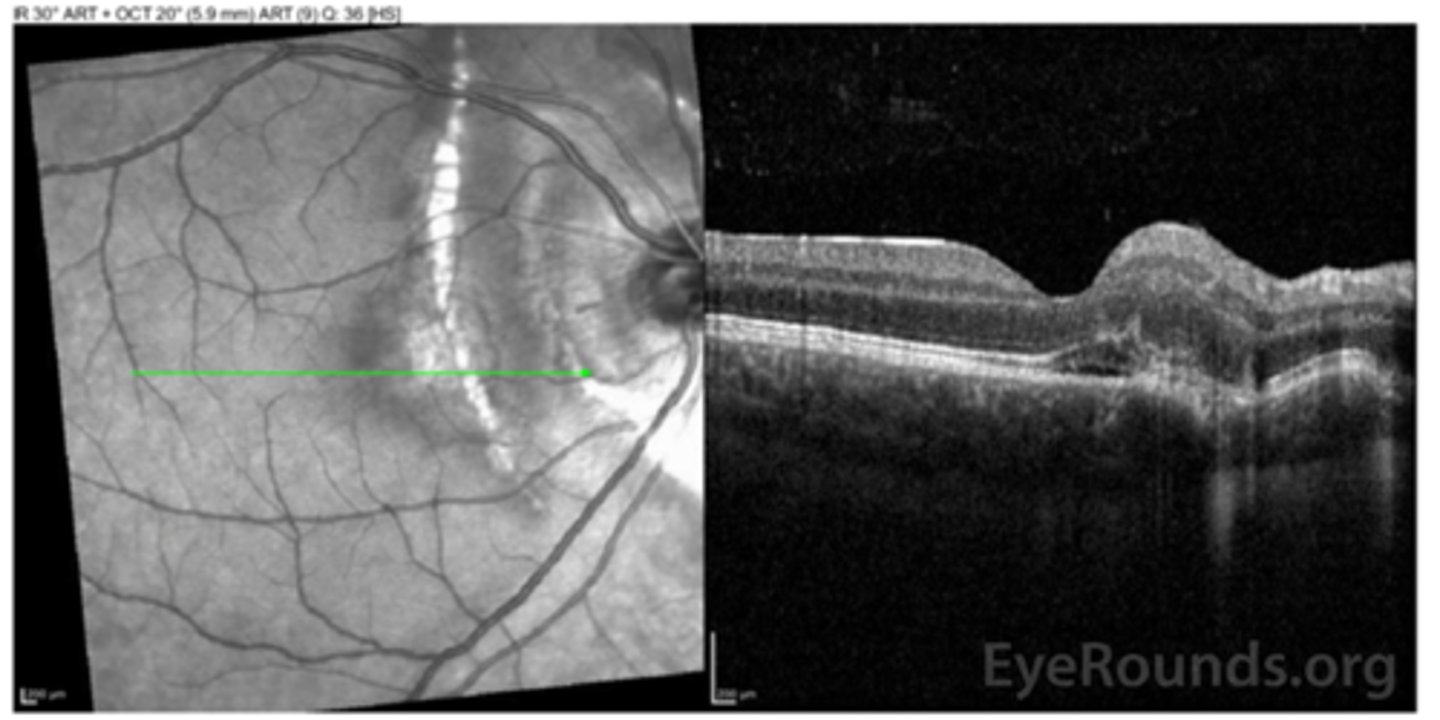

How does choroidal rupture appear on OCT here?

loss of RPE continuity at site of rupture = inner choroid atrophy

How does choroidal rupture appear on OCT here?

RPE disruption

+/- hemorrhage

What is seen in toxoplasmosis with OCT?

acute = retinitis = inflam, thickening of layers

acute = vitritis = dots and haze vitreous

chronic = necrotizing atrophy = scarring, thinning

How does ocular toxocariasis appear on OCT, as seen here in patient A?

multiple light granulomas = hyperR

How does ocular toxocariasis appear on OCT, as seen here in patient B?

recurrence = granulomas with exudates, edema

How does ocular toxocariasis appear on OCT, as seen here in patient C?

granuloma now in nasal retina, fibrous memb where granuloma once was (looks like ERM)